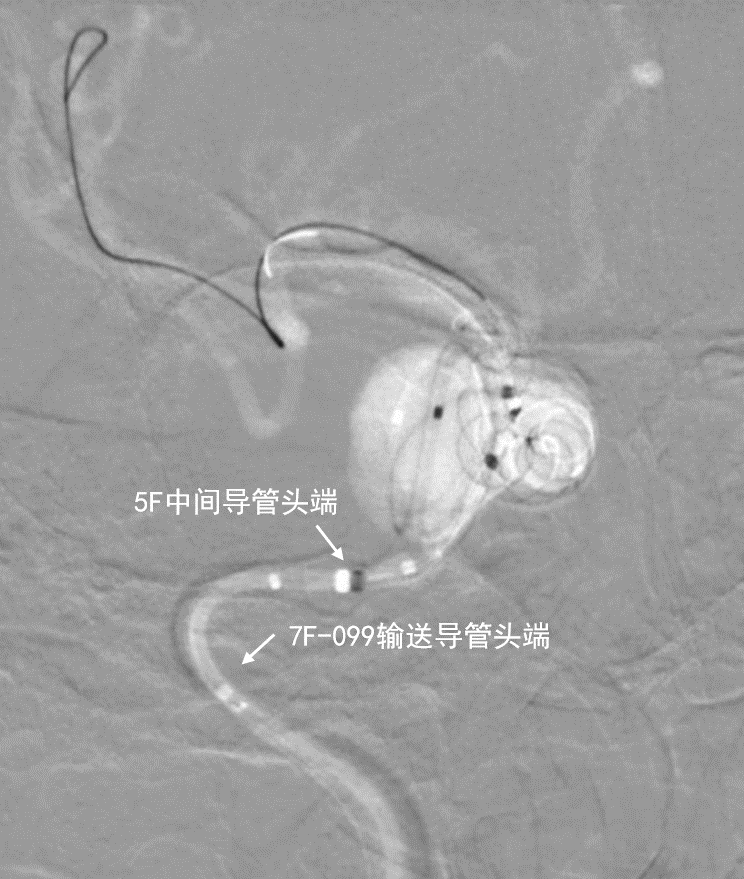

- 新路图下,沿微导管依次填入数枚弹簧圈,将动脉瘤填塞。复查造影证实动脉瘤达完全栓塞,载瘤动脉通畅。

动脉长鞘怎么置入深谋远路 | 千人皆翘首,万唤今始来——国内首款7F长鞘在血流导向密网支架联合弹簧圈栓塞治疗动脉瘤的首次应用_https://www.jmylbn.com_新闻资讯_第27张术后正位造影

术后侧位造影

深瑞达7F输送导管,中间导管和弹簧圈微导管的位置关系